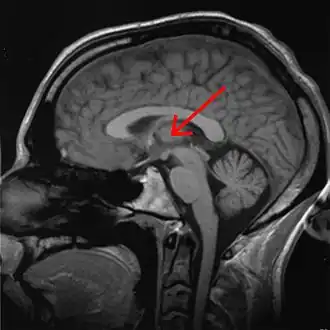

![]() Thalamus marked (MRI cross-section) | |